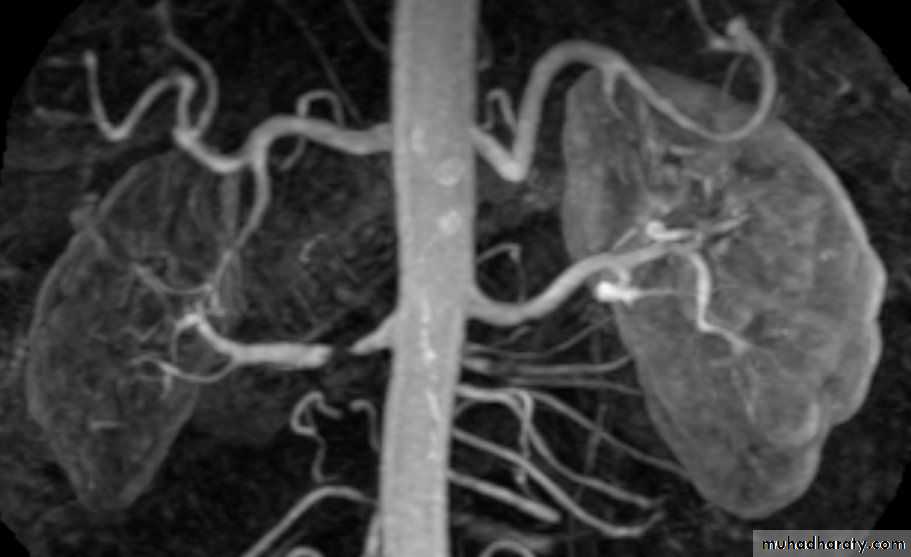

Renal MRA

• Renal artery stenosis

• IVC or renal vein extension of renal tumors.

The only parts of the renal tract which have enhanced are the renal arteries and the cortex.Useful for evaluation of the renal arteries (which may be reformatted as CT angiogram) and for evaluation of highly vascular renal tumors.